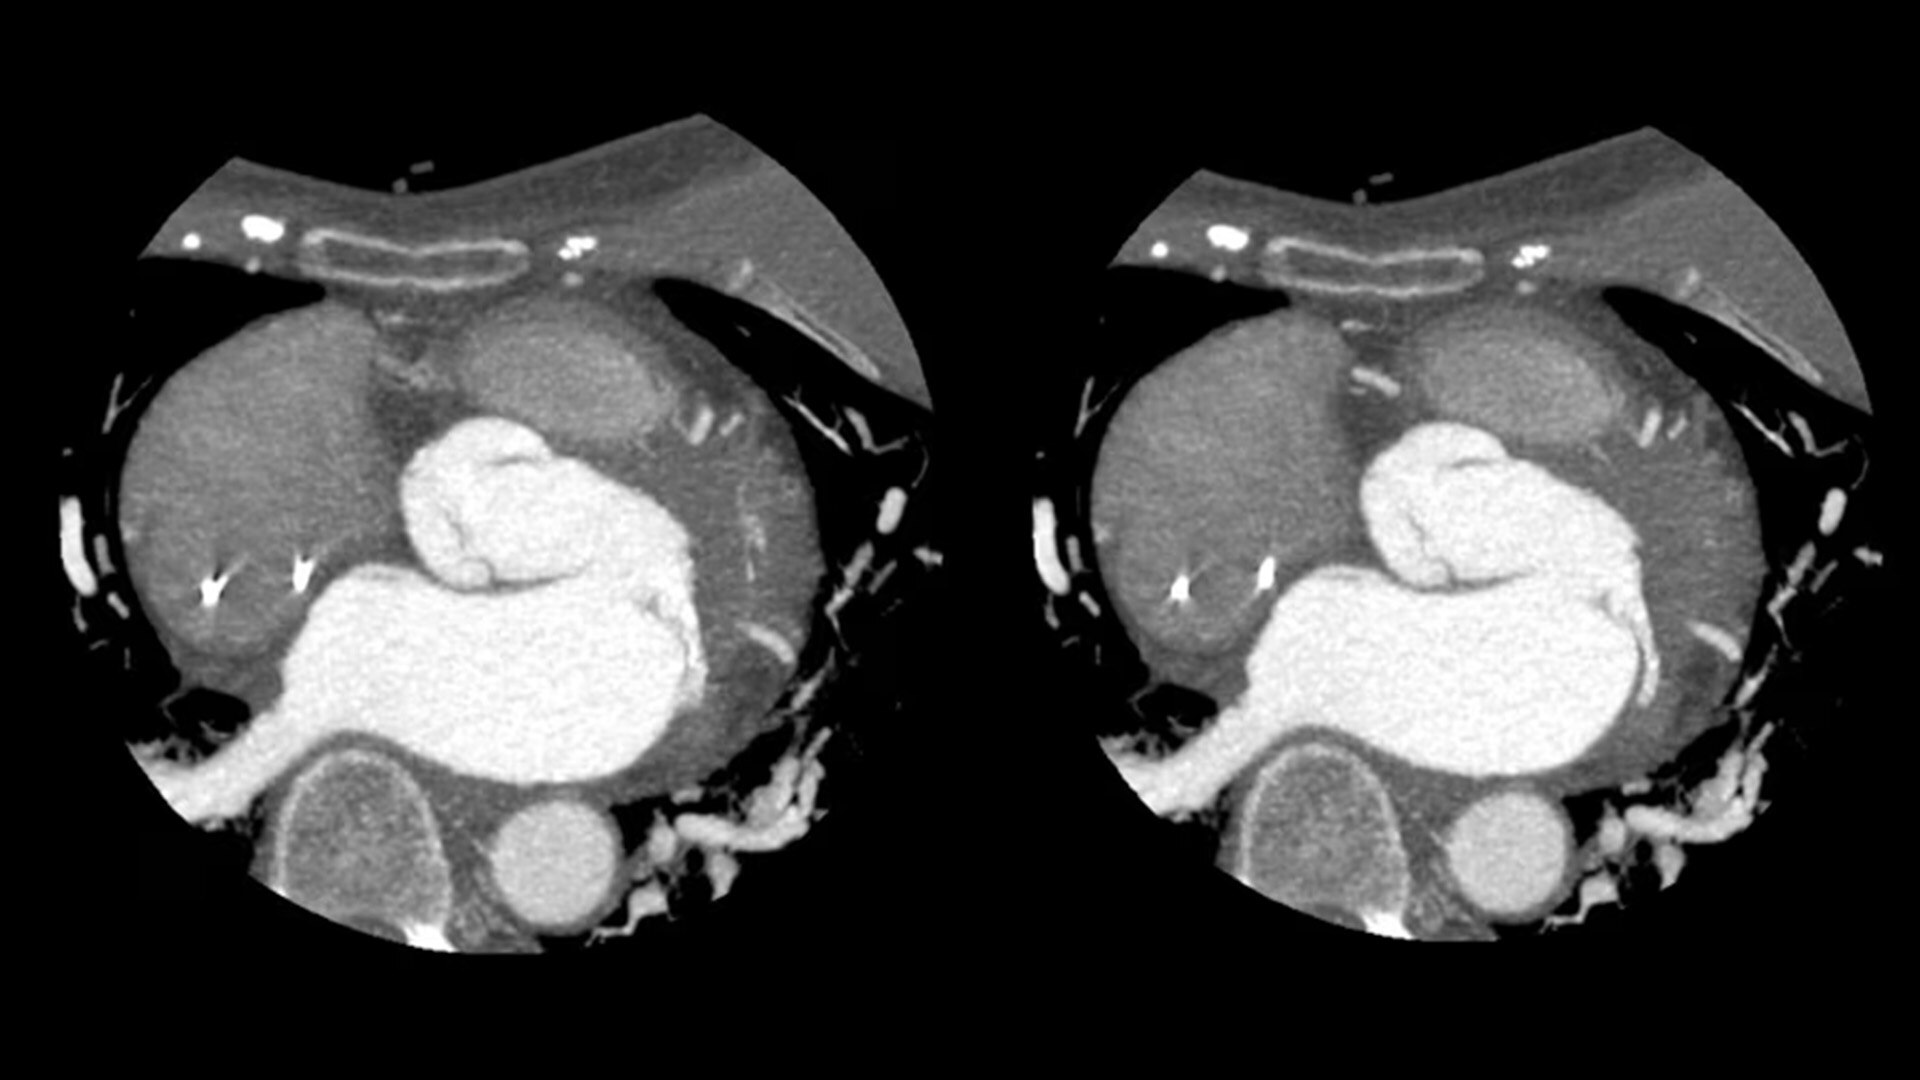

SnapShot Freeze 2

Intelligent and automated whole-heart motion correction for enhanced Cardiac CT imaging.

6x reduction in motion artifacts1

19.5 msec effective temporal resolution at 0.23s/rotation gantry speed2

1. As demonstrated in mechanical and mathematical cardiac phantom testing

2. SnapShot Freeze 2, in conjunction with 0.23 s/rotation gantry speed, provides a reduction in coronary motion artifacts that is equivalent to a 0.039 s/rotation equivalent gantry rotation speed with effective temporal resolution of 19.5 msec. As demonstrated in phantom testing using a commercially available motion phantom and also with a mathematical cardiac phantom with linear motion of variable velocity. The 0.039 s/rotation images are modeled without application of SnapShot Freeze 2. Results may vary in clinical applications.